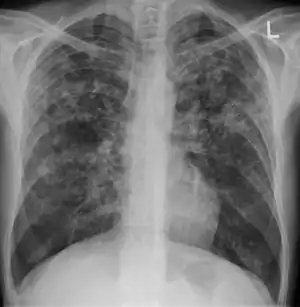

Miliary tuberculosis is a form of tuberculosis that is characterized by a wide dissemination into the human body and by the tiny size of the lesions (1–5 mm). Its name comes from a distinctive pattern seen on a chest radiograph of many tiny spots distributed throughout the lung fields with the appearance similar to millet seeds—thus the term "miliary" tuberculosis. Miliary TB may infect any number of organs, including the lungs, liver, and spleen.[2] Miliary tuberculosis is present in about 2% of all reported cases of tuberculosis and accounts for up to 20% of all extra-pulmonary tuberculosis cases.[3]

| Chest X ray showing miliary tuberculosis | |

Testing for miliary tuberculosis is conducted in a similar manner as for other forms of tuberculosis, although a number of tests must be conducted on a patient to confirm diagnosis.[5] Tests include chest x-ray, sputum culture, bronchoscopy, open lung biopsy, head CT/MRI, blood cultures, fundoscopy, and electrocardiography.[11] The tuberculosis (TB) blood test, also called an Interferon Gamma Release Assay or IGRA, is a way to diagnose latent TB. A variety of neurological complications have been noted in miliary tuberculosis patients—tuberculous meningitis and cerebral tuberculomas being the most frequent. However, a majority of patients improve following antituberculous treatment. Rarely lymphangitic spread of lung cancer could mimic miliary pattern of tuberculosis on regular chest X-ray. [16]